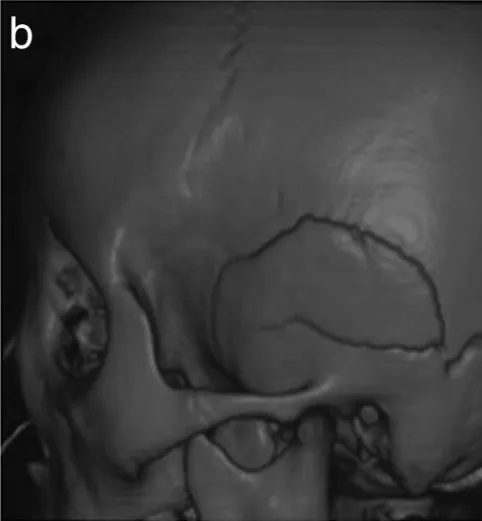

图b显示3D骨CT可见多发性颅骨骨折